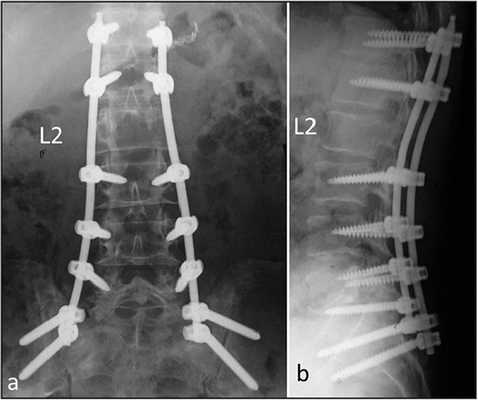

Последний этап транспедикулярной фиксации состоит в создании межтеловой компрессии при помощи специального инструмента и затягивания винтов. На ранее подготовленные декортицированные дуги и поперечные отростки выкладывается алло-или аутотрансплантат. Трансплантат используемый для создания спондилодеза можно смешивать с нативной смесью полученной в результате фильтрации интраоперационного отделяемого во время работы высокоскоростного бора. В конце операции выполняется рентгенологический контроль в 2-х проекциях.

Интраоперационная рентгенография поясничного отдела позвоночника после трансфораминального межтелового спондилодеза.